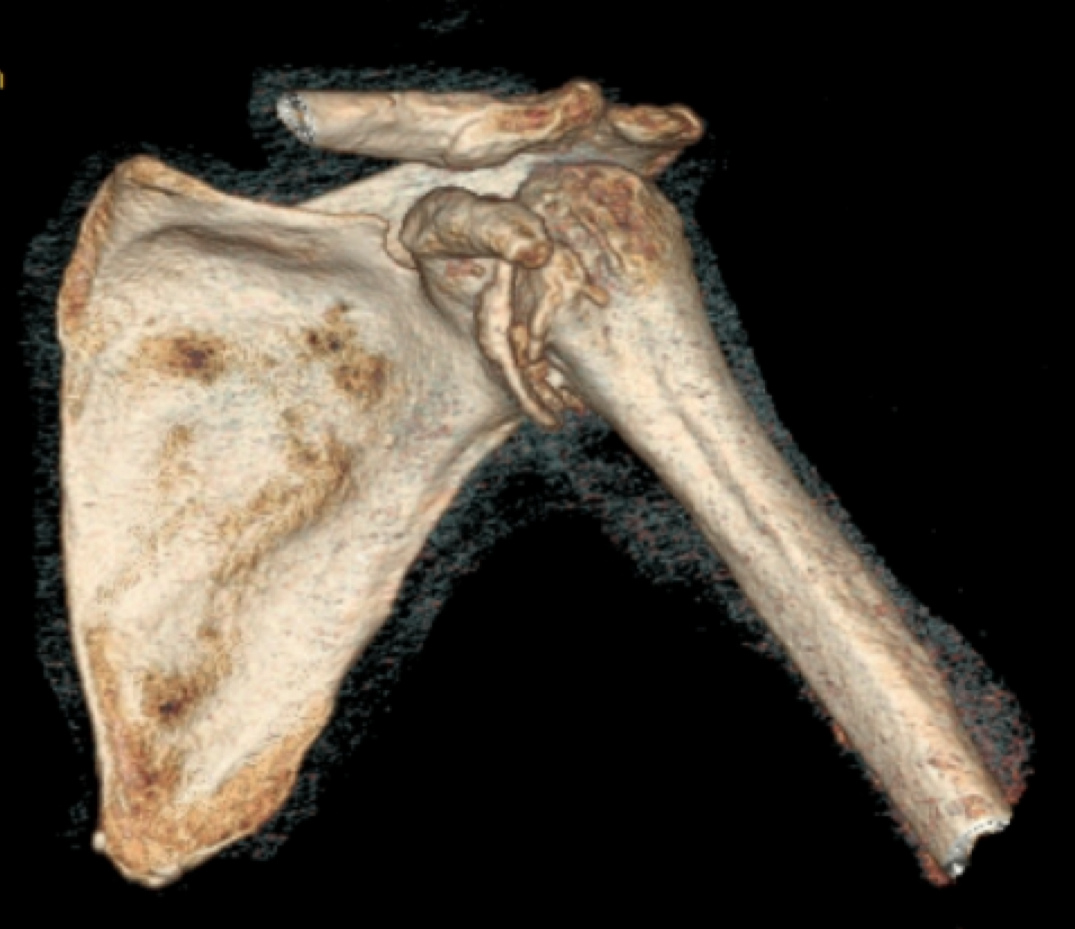

Pre-op

- Cuff tear athropathy

- Severe glenoid destruction

Surgical Plan

- Glenoid restoration with Bio RSA

- with appr. 10 mm thickness (allograft)

- Pre-op planning using the mediCAD 3D Shoulder Module